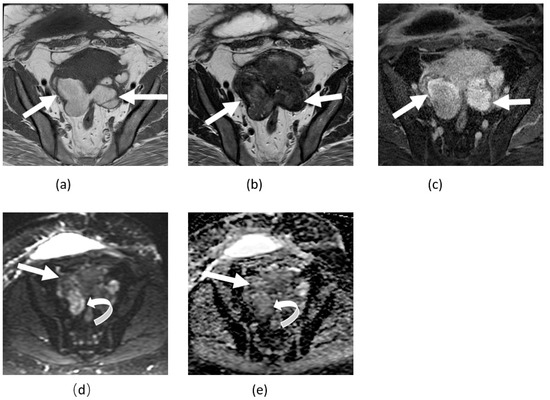

3.2. Adnexal Torsion

3.4. Tubo-Ovarian Abscess

3.5. Mature Cystic Teratoma

3.6. Ovarian Fibroma, Fibrothecoma, and Thecoma